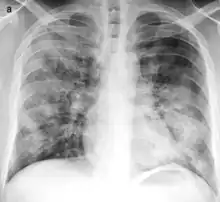

![]() | |

| Typical distribution of lobar pneumonia (left in image) and bronchopneumonia (right in image) | |